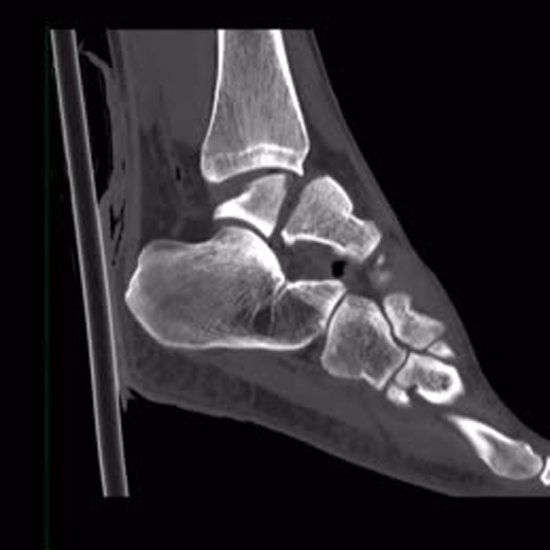

CECT (Contrast Enhanced Computed Tomography) Right Ankle Joint is an imaging

scan to assess the right ankle joint. This scan is used to evaluate the injury, fractures, dislocation, collective instabilities, and many other associated disorders. For this scan, you will be injected with contrast media and an x-ray beam to obtain the images of the right ankle joint.